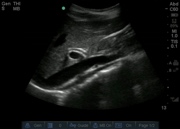

SONO 252 GB.